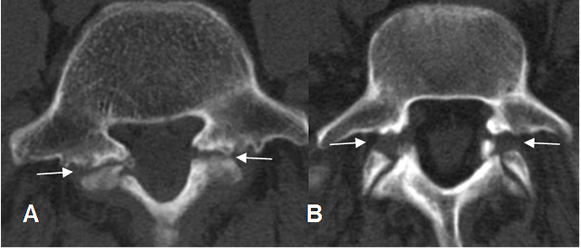

Se aprecia como imagen radiolúcida en la pars interarticular, con esclerosis de los fragmentos, mejor visto en una Rx oblicua. Puede ser uni o bilateral. En la TAC se encuentran los mismos hallazgos, en cortes por encima del nivel del disco. (1). (Fig 72 a 74).

Fig 73. Listesis.

A y B: TAC axial. Listesis bilateral sin desplazamiento en A y desplazada en B.